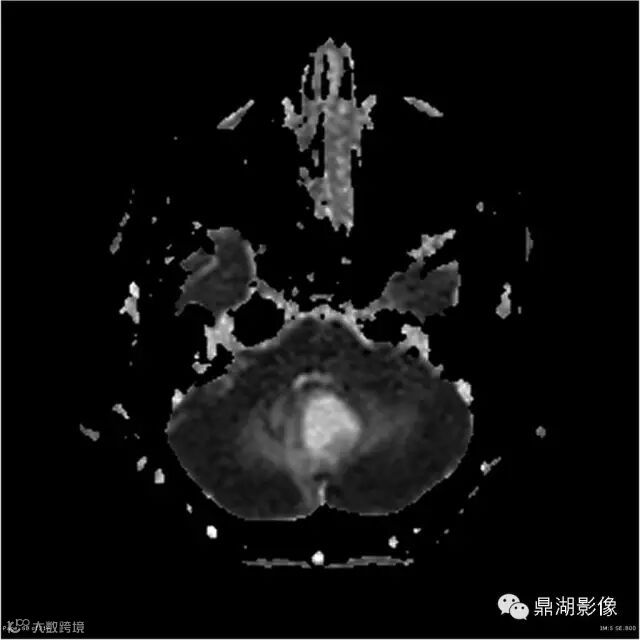

Axial ADC

本例为一例实质性血管母细胞瘤。实性血管母细胞瘤CT平扫示病灶呈等或高密度,增强后可见明显强化。MRI平扫通常病灶很不均质,T1呈稍低信号为主的较混杂信号,T2呈等、高信号,DWI通常呈低信号或等信号。文献报道,实性血管母细胞瘤较典型的表现为瘤内及瘤周扩张的流空血管影,瘤周中、重度水肿。因此,小脑半球区的单发肿块伴流空血管影,周围大片水肿以及增强后肿块明显强化"形态规则"边界清楚,此时应将实性血管母细胞瘤考虑在内。

实性血管母细胞瘤须与脑膜瘤、淋巴瘤、室管膜瘤等鉴别;脑膜瘤,为脑外肿瘤,极少发生囊变,多数可见“脑膜尾征”,出血及坏死少见,瘤周水肿较轻;淋巴瘤,常位于深部脑组织,无血管流空影,DWI上呈高信号,文献报道,实性血管母细胞瘤 DWI( b=1000) 呈低信号有助于两者鉴别;室管膜瘤一般瘤周无蚓状流空的肿瘤供血动脉,增强时强化程度不及血管母细胞瘤。